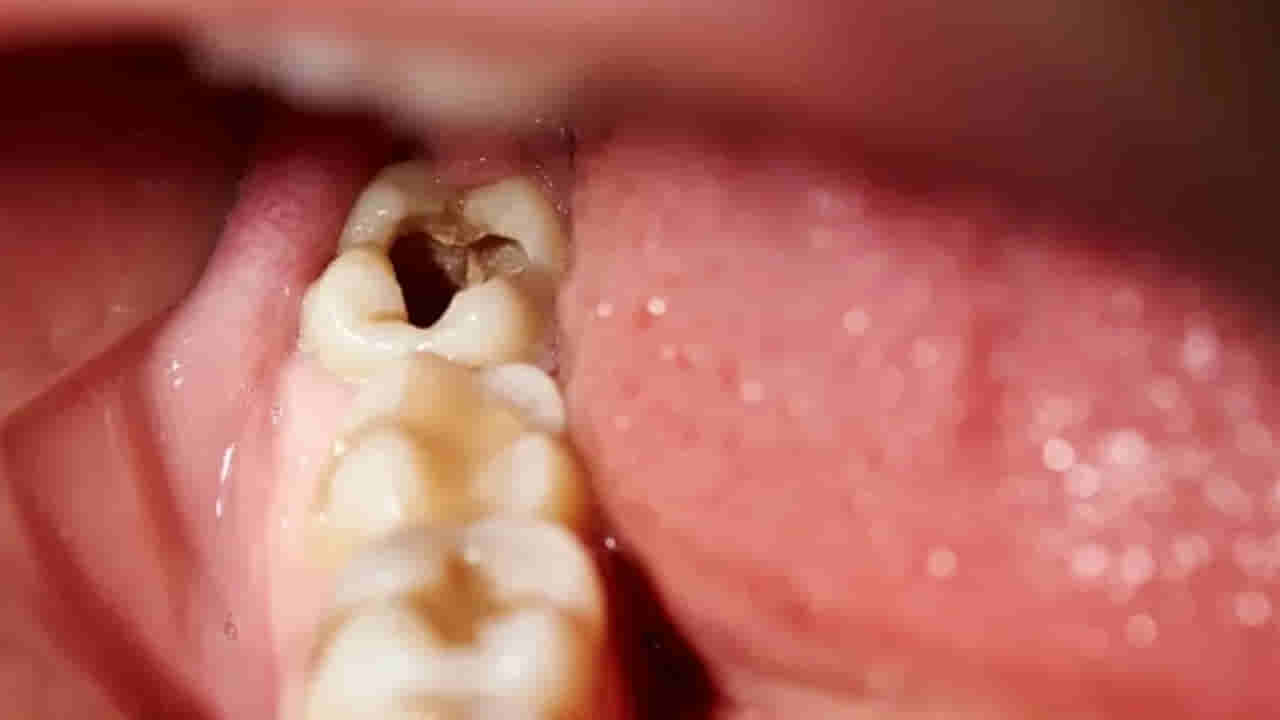

దంతాల ఆరోగ్యం, పంటి నొప్పి నివారణకు సంబంధించిన సంప్రదాయ గృహవైద్యాలు అందుబాటులో ఉన్నాయి. ఆధునిక దంత చికిత్సలు, ముఖ్యంగా రూట్ కెనాల్ వంటివి ఖర్చుతో కూడుకున్నవి, అందరికీ అందుబాటులో ఉండకపోవచ్చు. అటువంటి పరిస్థితుల్లో సహజ పద్ధతులు ఎంతో ప్రయోజనకరంగా ఉంటాయి. ఈ పద్ధతులు దంత సమస్యల నుంచి ఉపశమనం అందించడమే కాకుండా, దంతాలను దృఢంగా, ఆరోగ్యంగా ఉంచడానికి తోడ్పడతాయి.